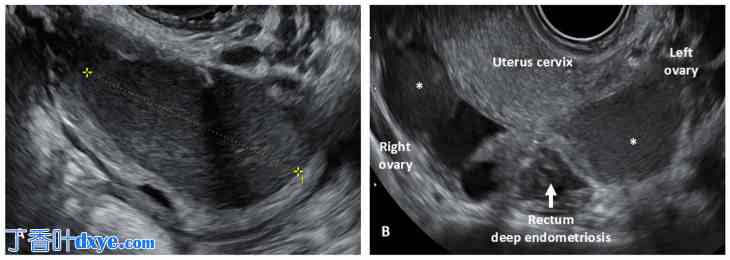

2015 年,一项共识确立了子宫腺肌病的超声征象 。2022 年,MUSA 小组对之前的 2015 年共识进行了回顾,并指出了子宫腺肌病的诊断有直接和间接征象。根据新的分类,可高度确诊子宫腺肌病的直接征象包括肌层内囊肿、高回声岛状结构、子宫内膜下或 JZ 区高回声线或芽状结构 (图 3)。

图 3.

子宫腺肌病的经阴道超声 (TVS) 表现。(A) 二维 (2D) TVS 评估显示直接诊断征象:子宫肌层囊性区域(黄色箭头)、高回声灶(带星号); (B)子宫腺肌病的三维(3D)TVS 评估显示弥漫性未定义的连接区。